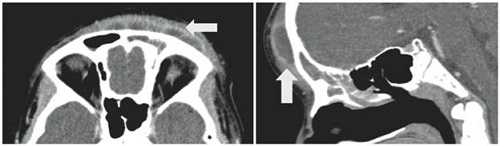

Caso 2

Paciente masculino de 12 años con cuadro clínico consistente en fiebre, cefalea, múltiples episodios eméticos y aparición de edema en región frontal de 3 días de evolución. Se hizo tomografía de cráneo con contraste, en la que se observó sinusitis frontal, etmoidal bilateral, maxilar izquierdo y esfenoidal, asociado a celulitis de predominio frontal.

Se consideró que cursaba con celulitis facial y se inició manejo antibiótico. Sin embargo, el aumento del edema en región frontal obligó a proceder con ultrasonografía, la cual reportó edema de los tejidos blandos y solución de continuidad de la tabla ósea. Así, se sugirió la presencia de pseudotumor inflamatorio de Pott. Por lo tanto, se solicitó nueva tomografía de cráneo contrastada, que mostró colección subperióstica a nivel frontal con erosión de la tabla anterior del seno frontal izquierdo y sin compromiso intracraneal.

El servicio de ORL realizó drenaje de absceso subperióstico y toma de muestras. El cultivo del seno frontal no arrojó microorganismos. No obstante, la muestra de seno maxilar izquierdo reportó S. epidermidis y Eikenella corrodens. Se continuó con esquema antibiótico por cuatro semanas y como resultado el paciente evolucionó de manera satisfactoria (Figura 2).